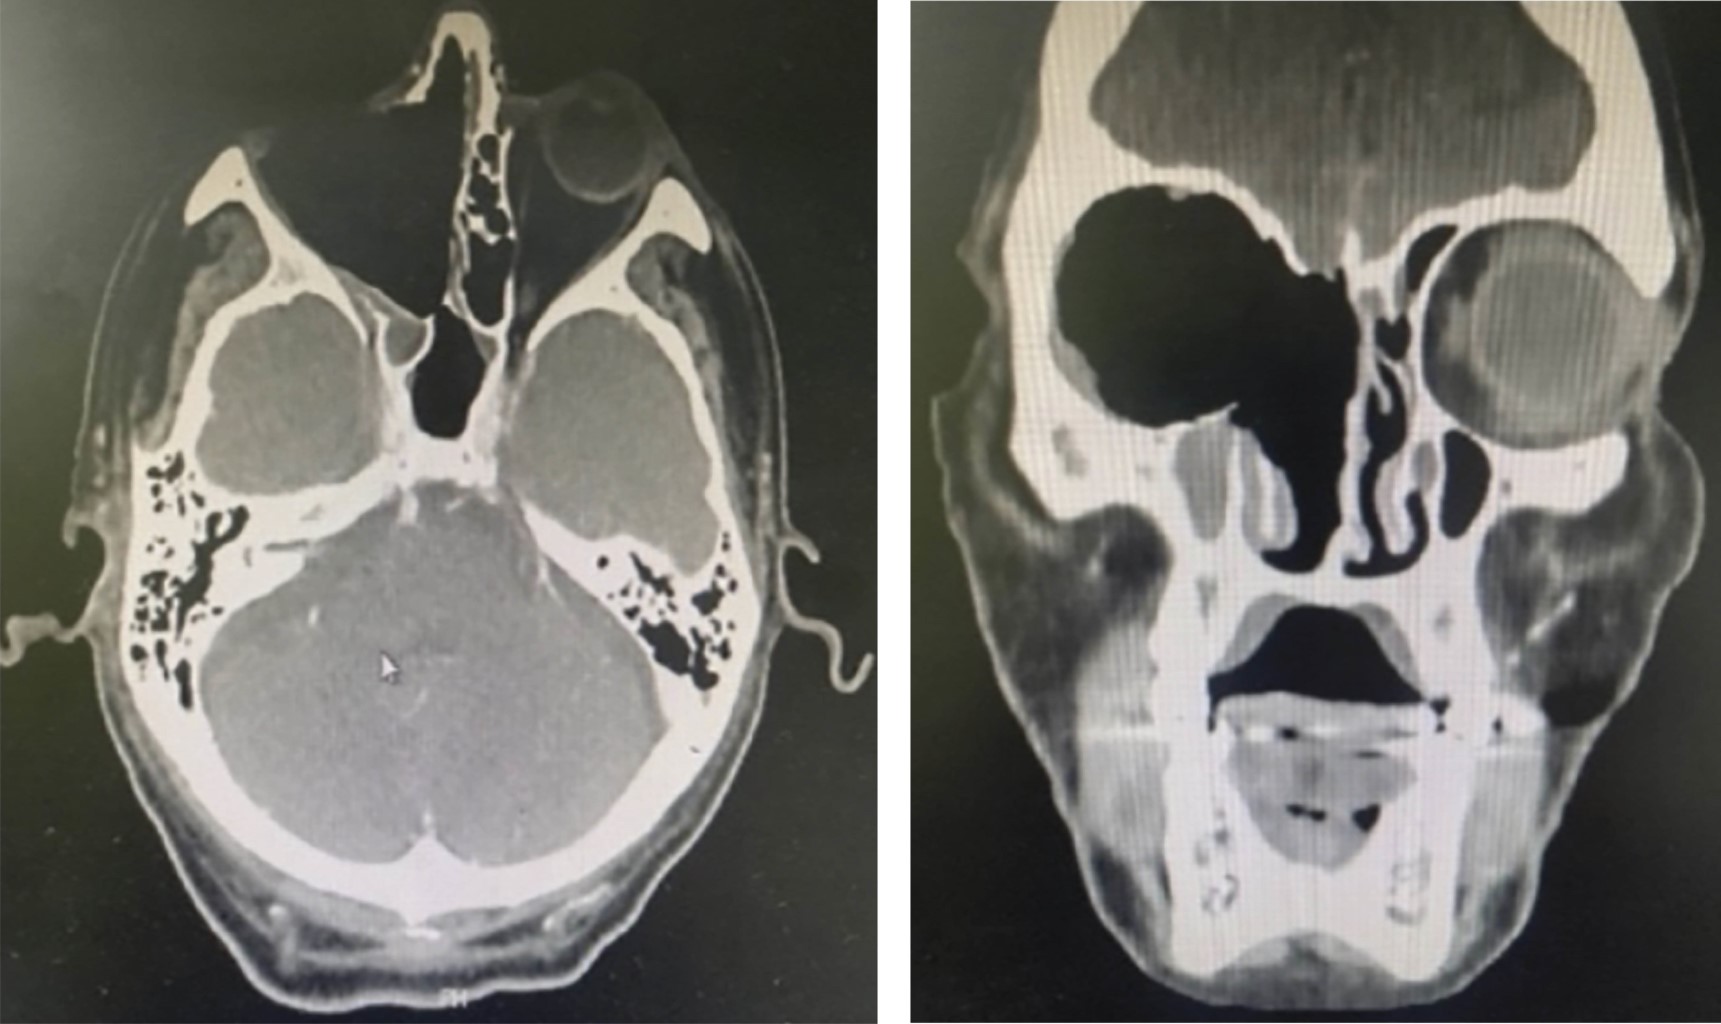

Se practica estudios micológicos de la secreción, observándose en el examen directo hifas hialinas no tabicadas (cenocíticas) confirmándose mucormicosis, se inicia tratamiento por el servicio de infectología con anfotericina B liposomal 60 mg intravenoso cada 24 horas (día 8), con adecuada respuesta mucocutánea, con limitación de infiltración. La tomografía axial computarizada muestra senos paranasales ocupados sin compromiso cerebral (Figura 3). Se realiza exenteración orbitaria derecha más cirugía funcional de nariz y senos paranasales (día 9). En la anatomía patológica, se observa en los tejidos elementos micóticos consistentes en hifas con las características citadas (Figura 4). Es valorado por cirugía maxilofacial y neurocirugía refiriendo no ser candidato a mayor tratamiento quirúrgico, presentando adecuada evolución con remisión de sintomatología inicial.

Figura 1

Figura 3